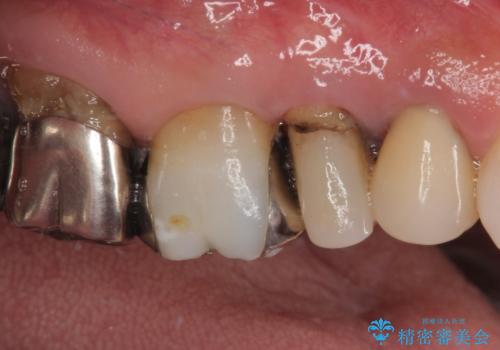

最新の症例

Latest cases